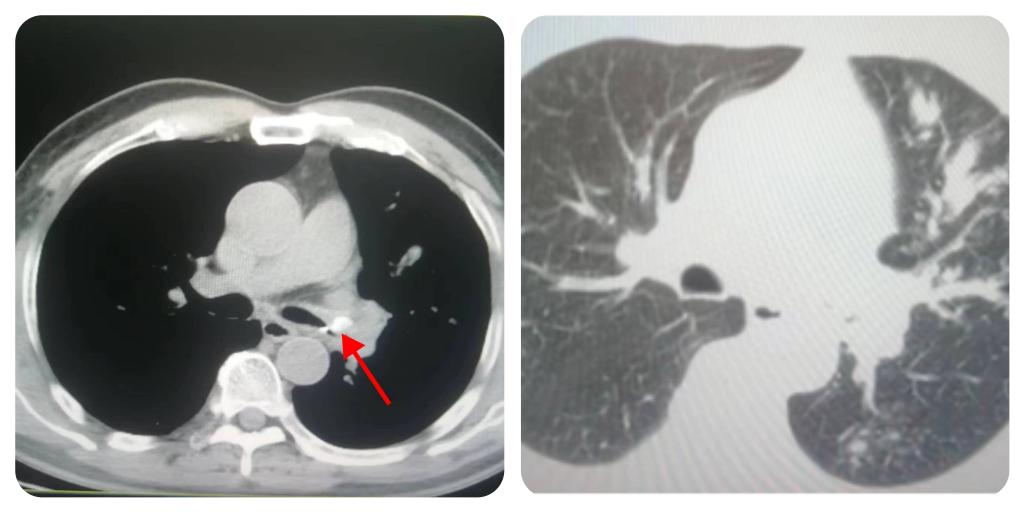

近日,井冈山大学附属医院呼吸与危重症医学科收治了一位“反复咳嗽咳痰3年”的63岁男性患者。近3年来该患者反复咳嗽咳痰,多次前往医院就诊,经抗炎等治疗有所好转,但反复发作。这次来医院就诊,行胸部CT检查示:左肺上叶阻塞性肺炎,不能排除恶性肿瘤的可能,故收至我科住院,入院后给予积极抗感染、化痰等治疗,但治疗效果不佳经。呼吸与危重症医学科主任高雪萍、古群英副主任医师、主治医师肖越、李发平重新对该患者病情进行梳理,共同讨论研判后,考虑可能为气道异物。

气道异物 左侧阻塞性肺炎